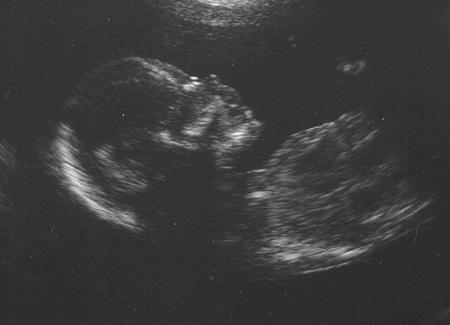

Julian's first photo!

Currently, I'm 26 weeks old but I'm making my mom look like she is going to pop. She thinks she's uncomfortable! I have a big brother that's already smacking me and trying to take over my space. I have to teach that guy a thing or two once I'm born.